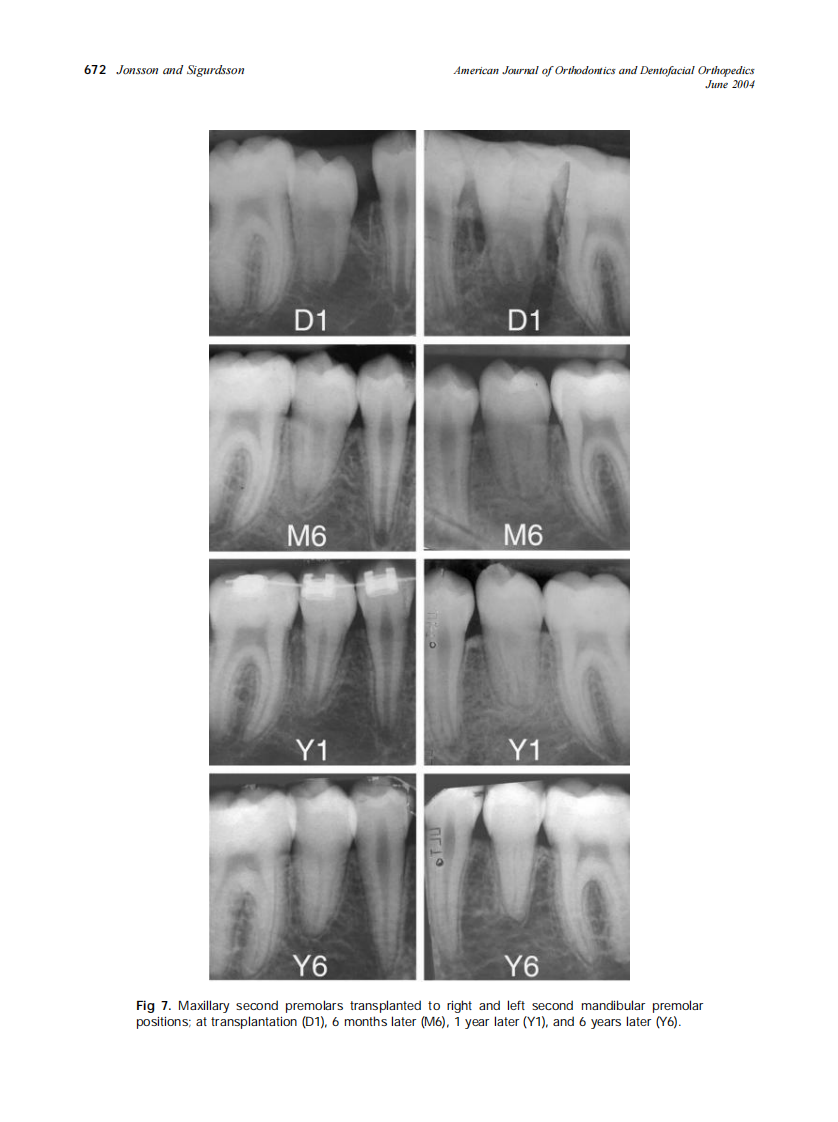

2004_125_6_668_675_Jonsson.pdf